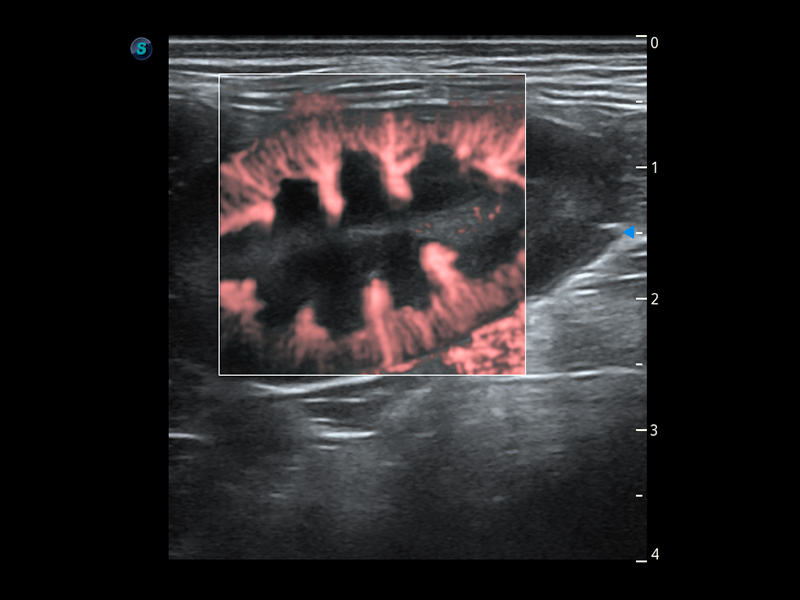

PDI 能量多普勒血流

提供高灵敏度和空间分辦率的血流图像,获得更加真实和丰富的诊断信息。

Bright Flow 立体血流成像

在传统二维血流成像的基础上,呈现血流的立体感,具有动感的生命力之美。精确区分不同血管的空间关系,提高了血流的视觉敏感性。

优异的基础图像

(犬)肾脏血流